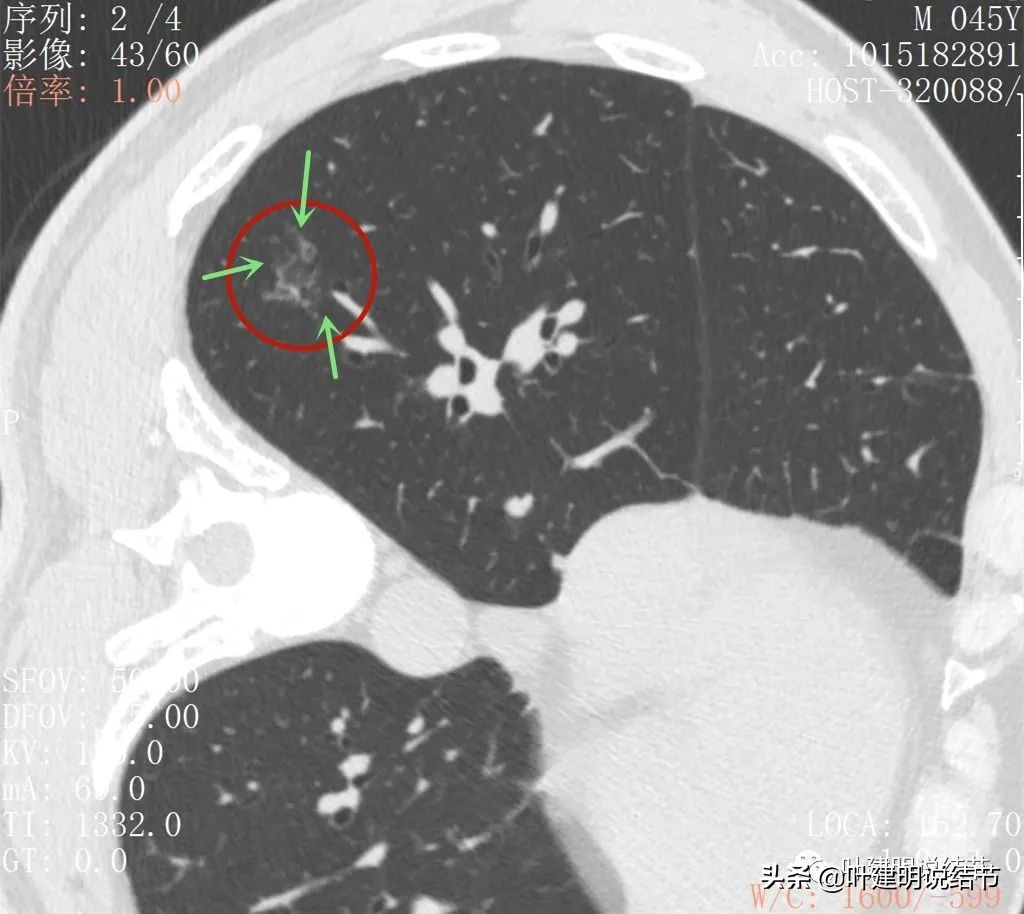

再来看薄层扫描:

病灶感觉很散在,但内部有扩张的细支气管(黄色箭头)、边缘略显不清(绿色箭头),部分有偏实性(粉色箭头)。

边缘血管异常增粗(桔色箭头),边缘显糊(绿色箭头),细支气管扩张(黄色箭头)

病灶似乎非圆形或类圆形,扩张的细支气管壁密度偏高(蓝色箭头),感觉比较僵硬(黄色箭头),病灶轮廓显模糊(黄色箭头)

扩张细支气管壁密度较高,病灶轮廓显糊

病灶边缘部分